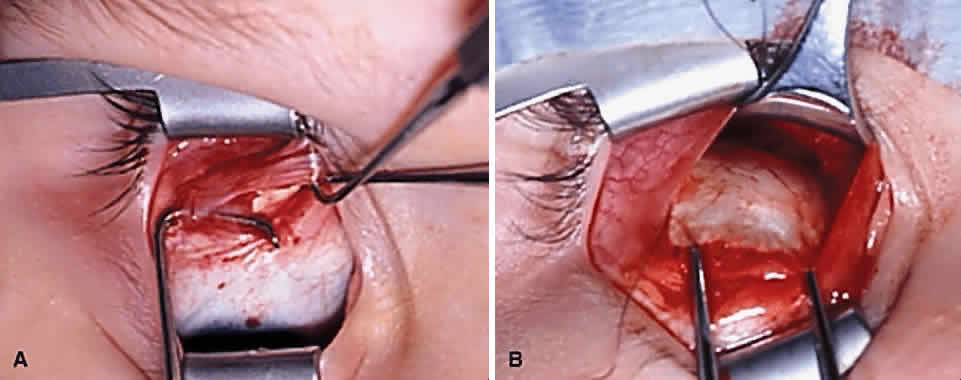

Serious complications of superior oblique muscle strengthening are infrequent. Intraoperative complications relate primarily to orbital hemorrhage from injury to a vortex vein or unintended entry into the orbital fat space, which results in an adherence syndrome with restricted ductions postoperatively. These can be avoided by good surgical exposure, use of loupe magnification with a surgical headlight, and deliberate and meticulous surgical technique. The superior oblique tendon can be surgically missed or inadvertently cut during dissection of the intermuscular septum. Anatomic variations including absence of the tendon are common.12 Confusion can also occur if the surgeon inadvertently engages the superior oblique tendon when first attempting to hook the superior rectus muscle.49 However, this is less common when the superior oblique tendon is approached temporally rather than nasally (Fig. 9). Surgical overcorrection occurs frequently, but it is fortunately not permanent in most patients. However, permanent overcorrection that results in a primary gaze position hypotropia is usually an unacceptable result and requires reoperation. It can be caused by excessive surgical dosage, spontaneous recovery of superior oblique muscle function, or failure to recognize bilateral superior oblique muscle palsy preoperatively.

Iatrogenic Brown's syndrome is an unavoidable complication of superior oblique muscle strengthening and occurs in almost 100% of patients undergoing superior oblique tendon tuck. It is virtually identical in clinical appearance to congenital Brown's syndrome, which is discussed later in this chapter (Fig. 10). In the absence of excessive tendon shortening, the limitation of elevation in adduction almost always improves with time and reoperation for this entity is rarely required. Tendon tucking medially (rather than temporally) to the superior rectus muscle is more hazardous because of proximity to the trochlea. Patients with persisting overcorrection in primary gaze position and at least moderate Brown's syndrome (no elevation above the horizontal meridian in adduction) are usually symptomatic and should have their tucks removed. However, adhesions between the superior rectus muscle, superior oblique tendon, and the globe are likely to be present and must be freed to normalize ductions. In general, tuck take down should be performed without simultaneous surgery on other cyclovertical muscles.